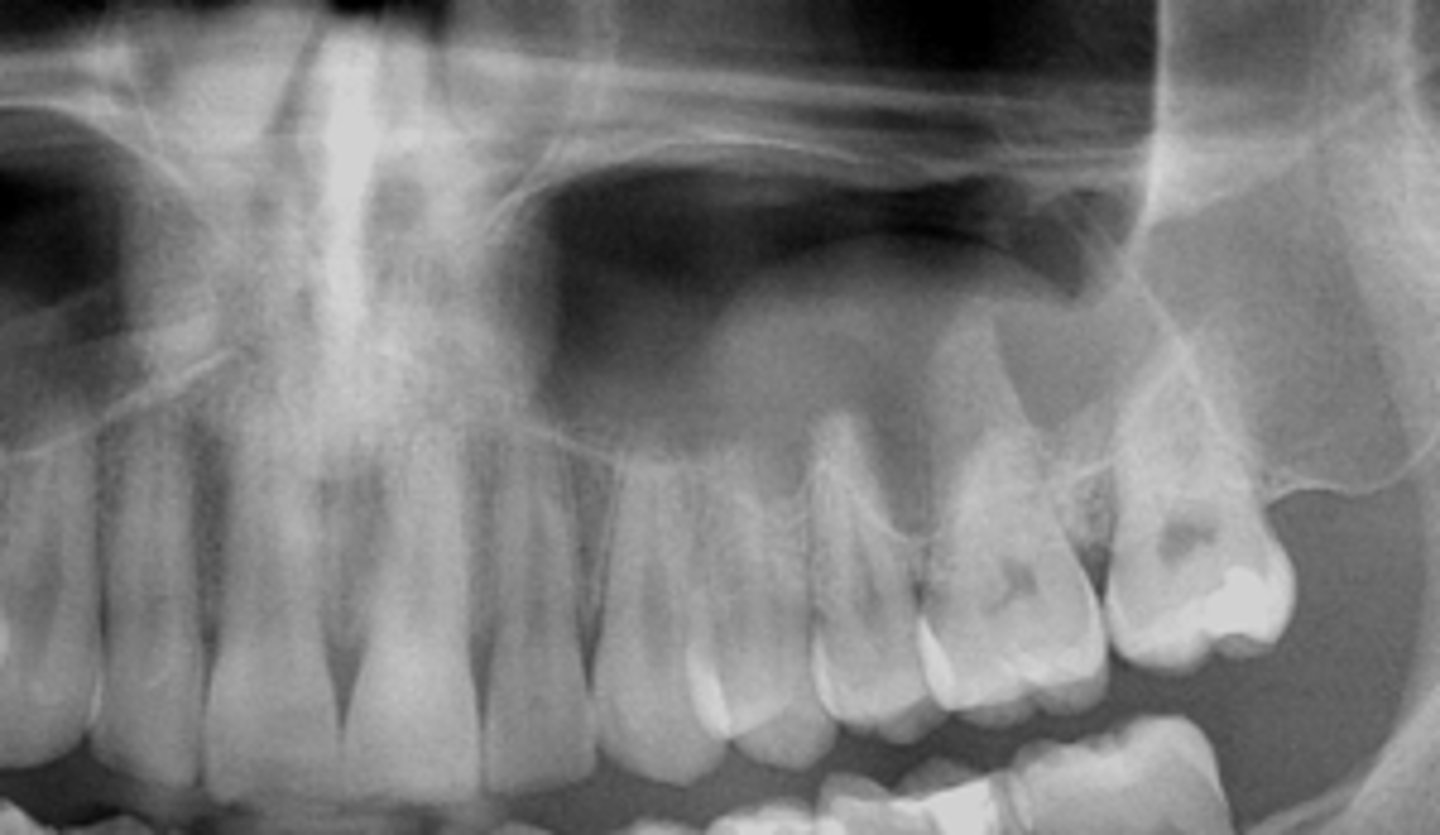

how would you describe this lesion? (not the giant cavity btw)

A. defined, corticated, periapical radiolucency causing loss of lamina dura and PDL space on #6-7

B. defined, non-corticated, periapical radiolucency causing loss of lamina dura and PDL space on #6-7

C. ill-defined, circular radiolucency located above tooth #7

D. well-defined, corticated, radiopacity

- Also note epicenter located above apex # 7 which has large dental caries.

What category would this lesion be part of?

Inflammation/benign

all of the following could be a differential diagnosis for the following lesion EXCEPT?

A. radicular cyst

B. Periapical granuloma

C. apical rarefying osteitis

D. renal osteodystrophy

what category would this lesion be classified into?

inflammatory/benign cystic